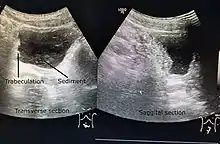

A paraplegic patient with neurogenic bladder on regular ultrasound follow-up showing thickened bladder wall with trabeculations and sediments within the bladder.

Ultrasound imaging can give information on the shape of the bladder, post-void residual volume, and evidence of kidney damage such as kidney size, thickness or ureteral dilation.[9] Trabeculated bladder on ultrasound indicates high risk of developing urinary tract abnormalities such as hydronephrosis and stones.[10] A voiding cystourethrography study uses contrast dye to obtain images of the bladder both when it is full and after urination which can show changes in bladder shape consistent with neurogenic bladder.[9]